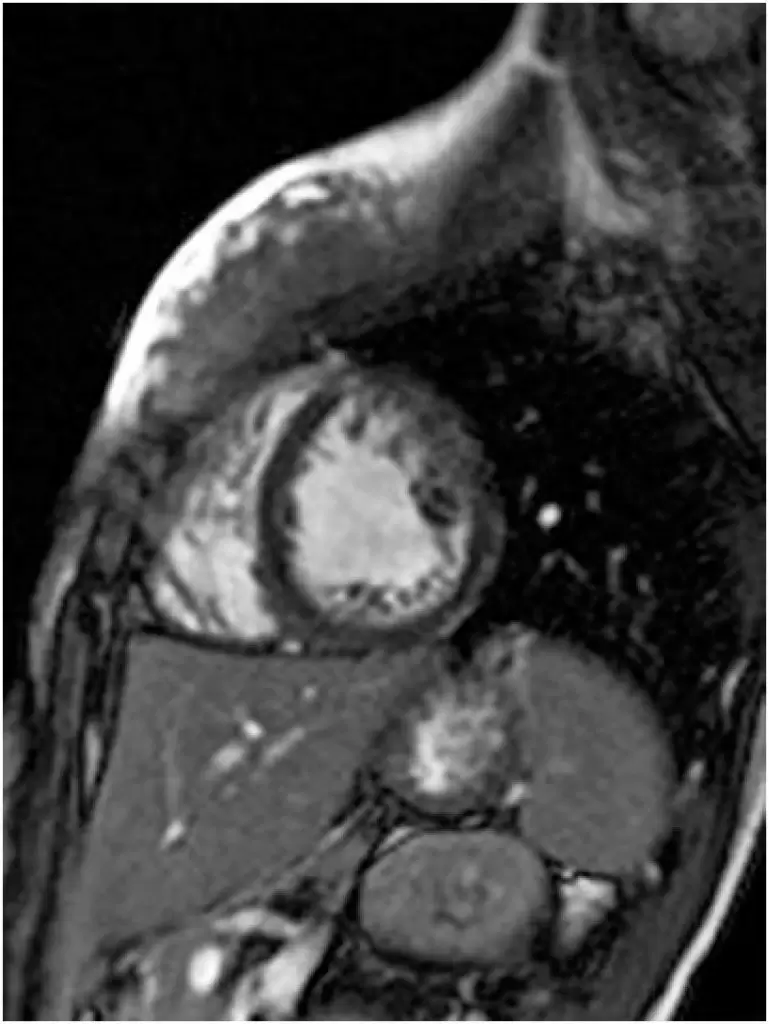

O miocárdio não compactado é uma cardiomiopatia congênita caracterizada pela presença de trabeculações anormais no ventrículo esquerdo. O presente estudo descreve o caso de uma paratleta de goalball, 14 anos, sexo feminino, assintomática, com história pessoal de nistagmo congênito e leve deficiência visual, que apresentou alterações eletrocardiográficas inespecíficas durante avaliação pré-participação. A ressonância magnética cardíaca evidenciou presença de não compactação miocárdica (relação entre camada não compactada/camada compactada igual a 2,5) e disfunção sistólica biventricular leve. Inicialmente, a paciente foi afastada da prática de esportes, e o seguimento clínico foi realizado a cada 3 meses. A paciente permaneceu assintomática durante o período de 1 ano de seguimento, sem história de síncope inexplicada, comprometimento significativo da função sistólica ou taquiarritmias ventriculares importantes ao teste de esforço. Por fim, ela foi liberada para prática competitiva de goalball, e o seguimento clínico foi mantido a cada 6 meses. Não há consenso quanto aos critérios de elegibilidade para a prática esportiva nos casos de miocárdio não-compactado. Assim, é prudente individualizar a decisão quanto a prática esportiva, bem como considerar a participação em esportes competitivos para indivíduos assintomáticos e sem repercussões da doença.